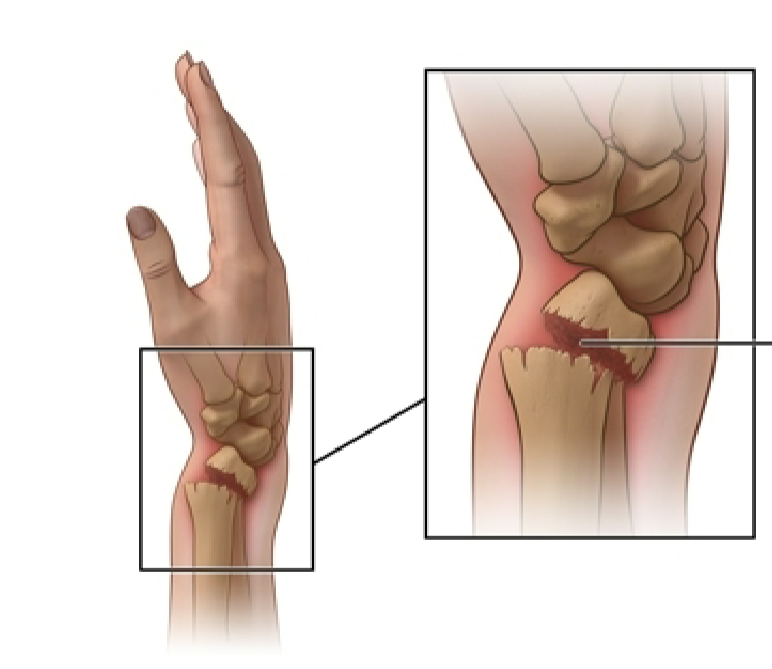

What kind of fracture would this lead to?

Colles fracture